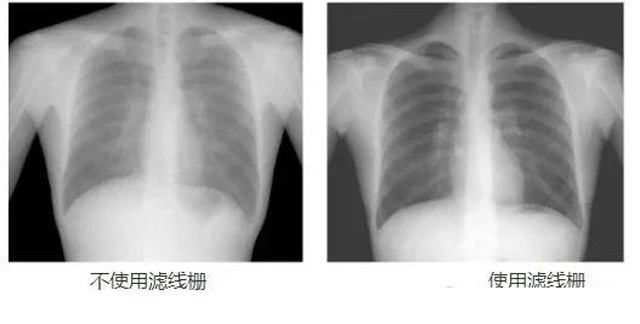

DR影像X射線在醫(yī)學(xué)檢查成像有著廣泛的使用。但是它的散射線影響成像質(zhì)量問題。濾線柵的發(fā)明使用很好的解決了這個(gè)問題,構(gòu)造簡單鉛條粗,密度和柵比規(guī)格單一,能減散射線但吸收較多原發(fā)射線。伴隨這醫(yī)療影像設(shè)備技術(shù)的發(fā)展,這個(gè)濾線柵的工藝制造技術(shù)有改進(jìn),鉛條變薄,柵密度和柵比有更多的選擇。特別是材料方面有新組合,填充物也依不同成像要求優(yōu)化。特別是移動(dòng)DR這類型的DR設(shè)備的出現(xiàn),濾線柵也設(shè)計(jì)成立方便拆卸形的,方便使用。被照體情況決定是否使用,更好平衡成像質(zhì)量與射線劑量。

放置方面:置于人體與片盒間,聚焦面朝向X線入射方向,X線焦點(diǎn)放鉛條會(huì)聚線上,不能反置,X線中心對(duì)準(zhǔn)濾線柵中心,左右偏移不超3cm,傾斜X線管要與鉛條排列方向平行。攝影時(shí)焦距改變不超焦距的25%;活動(dòng)式濾線器運(yùn)動(dòng)時(shí)間至少長于曝光時(shí)間的1/5;因吸收原發(fā)射線要適當(dāng)增加曝光條件;四肢薄位置一般不用濾線柵;不同千伏對(duì)應(yīng)不同柵比;立位胸片架、乳腺DR攝影等有各自特定濾線柵要求。